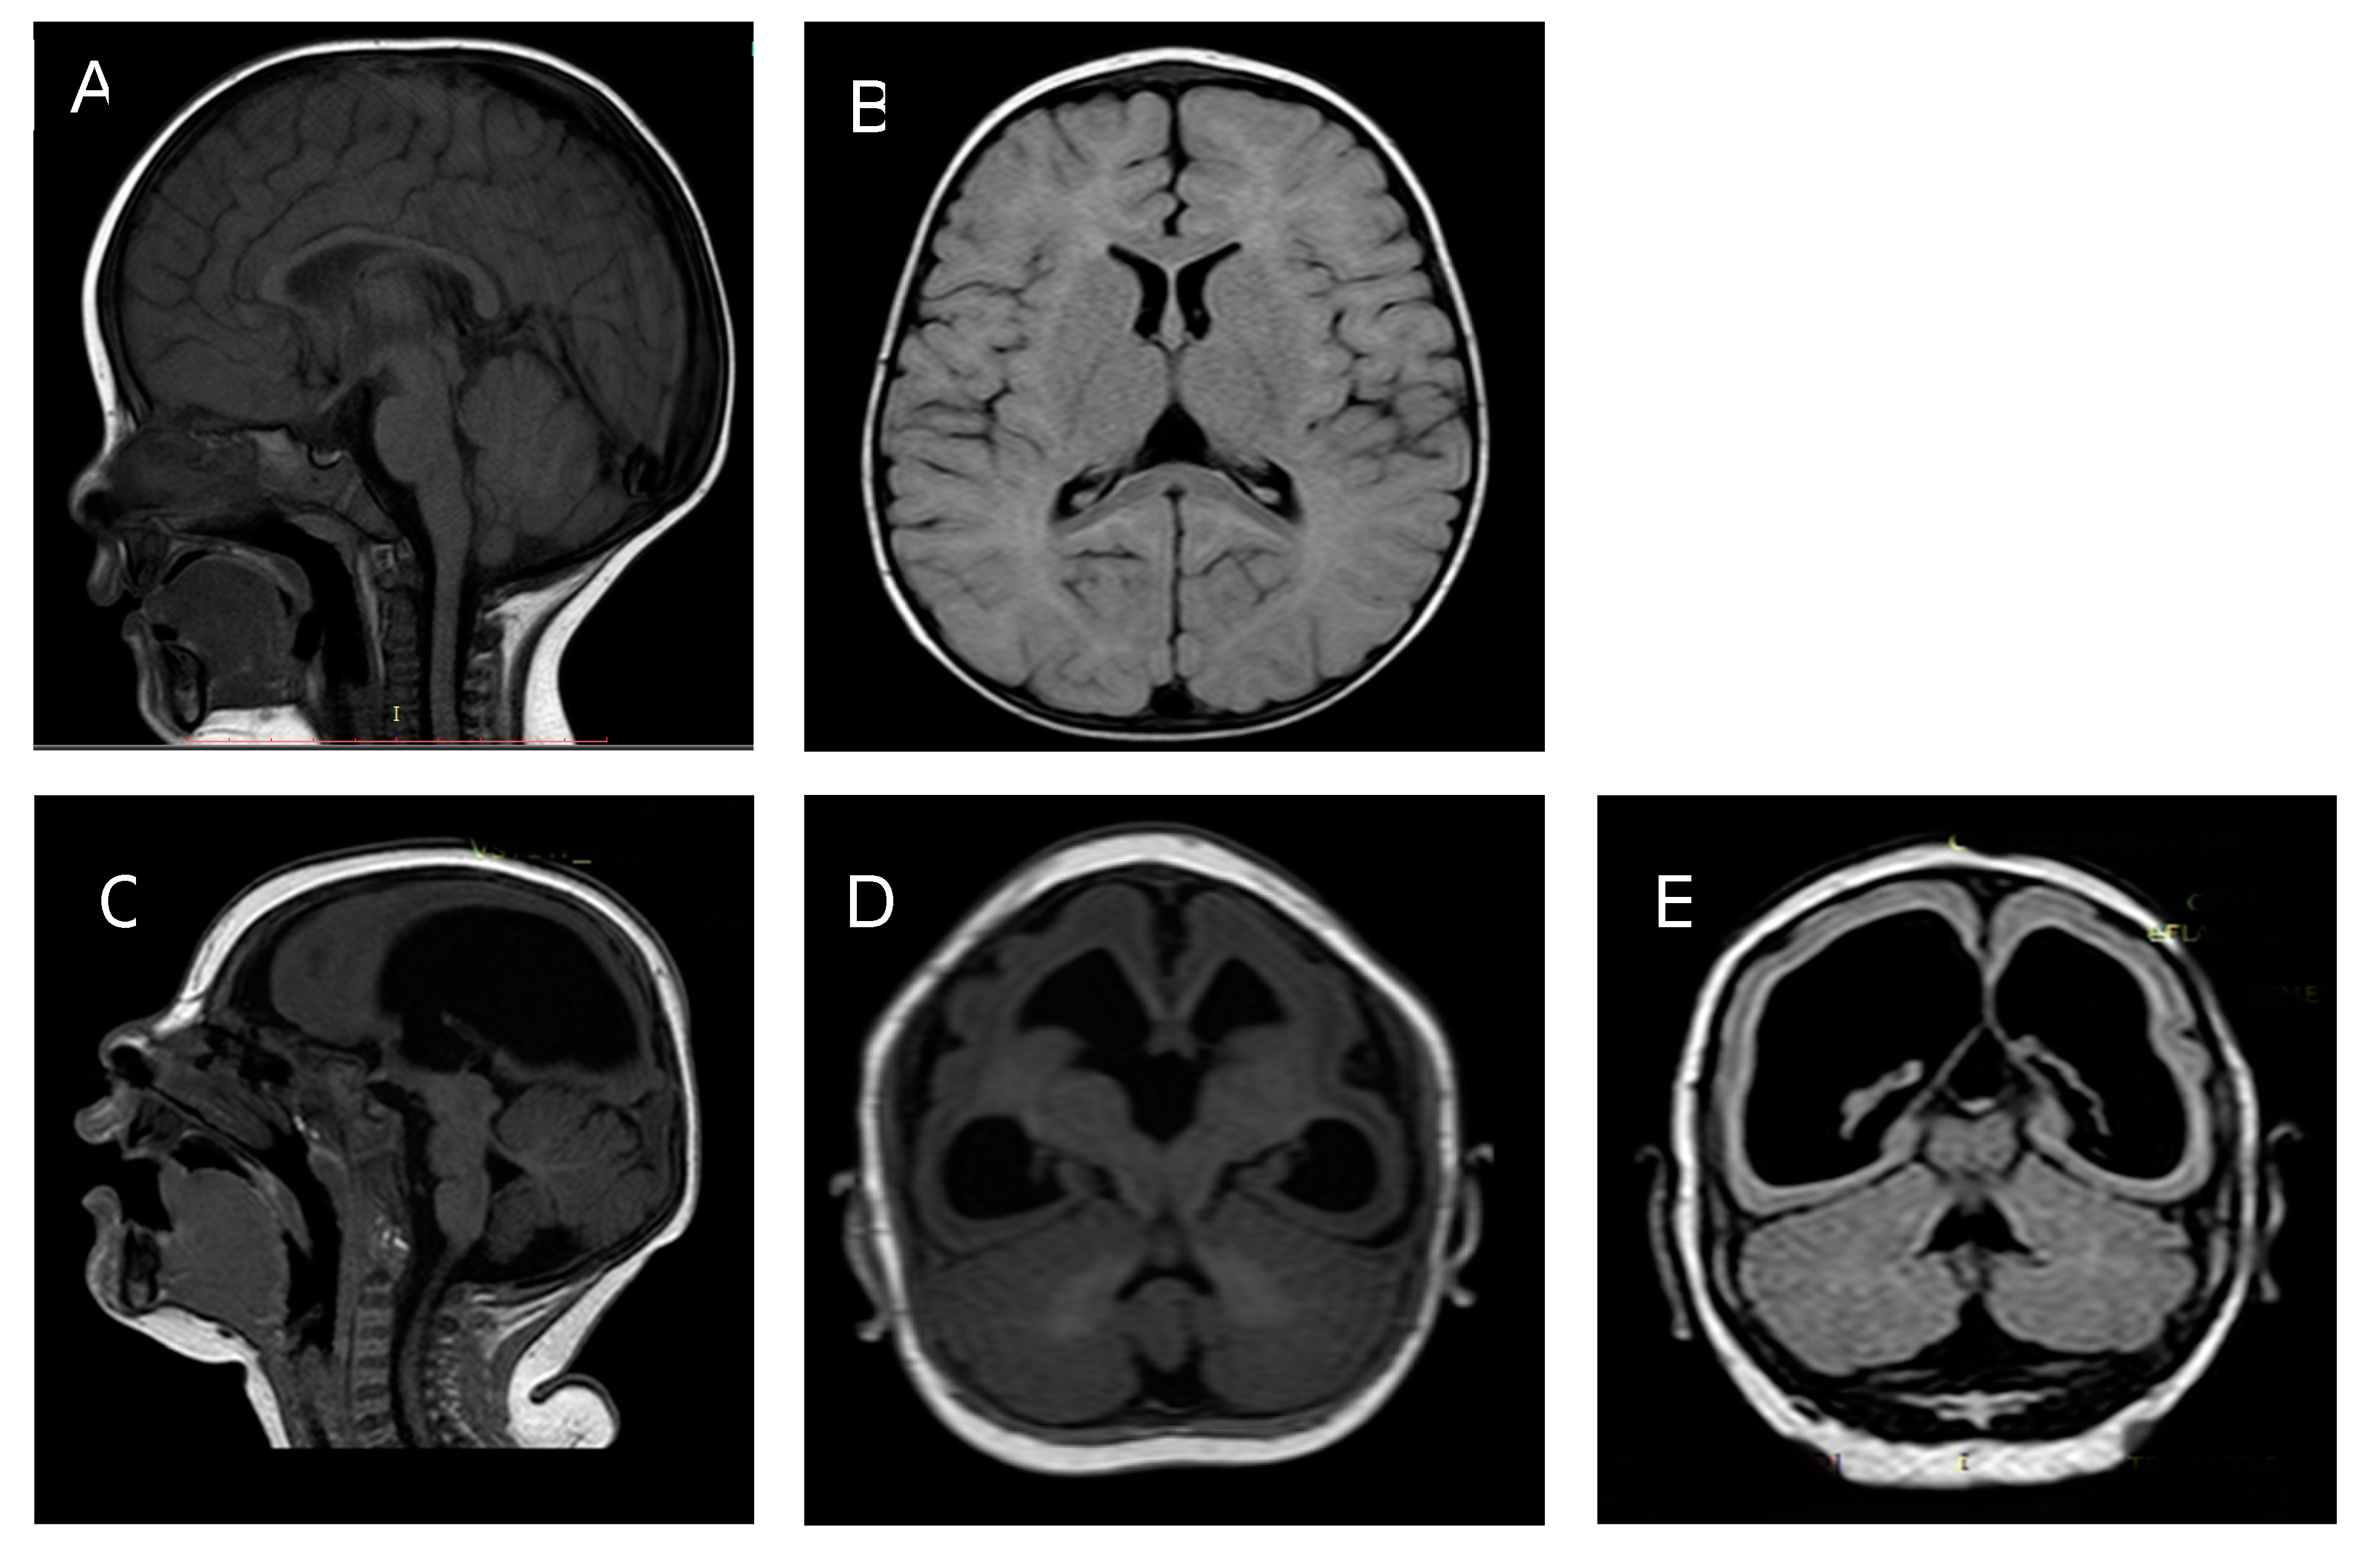

3.2.1. Twin A

3.2.2. Twin B